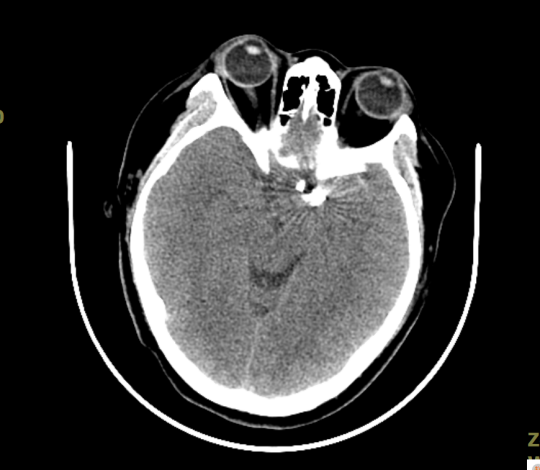

术后复查CT未见出血、梗死,术区见形态规则的弹簧圈影